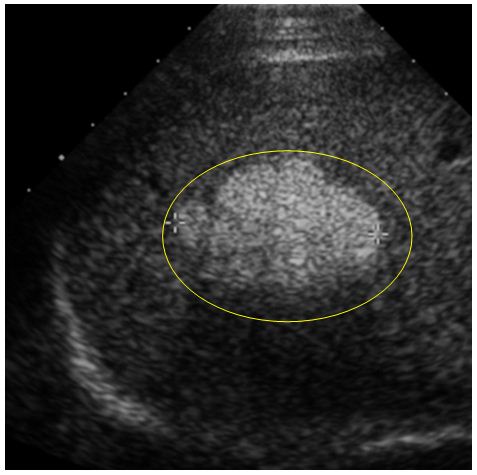

Bệnh nhân đã được chỉ định làm siêu âm ổ bụng. Kết quả siêu âm cho thấy có hình ảnh khối u ở gan phải, kích thước 6,8x7,5 cm, không có dịch ổ bụng, không có huyết khối tĩnh mạch cửa.

Hình ảnh siêu âm: khối tăng âm (trong vòng tròn màu vàng)